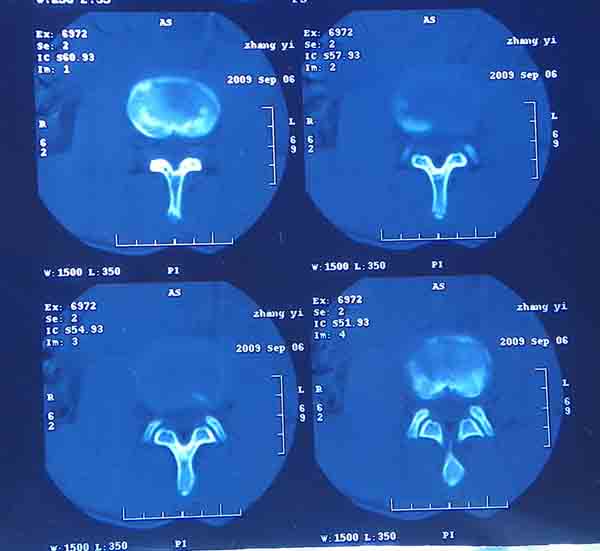

腰5/骶1椎间膨突出外,还有点异常,不知是什么东东,请各位大虾帮忙看看(12骨窗最明显)

椎体后缘软骨结节

软骨结节

支持 椎体后缘软骨结节。